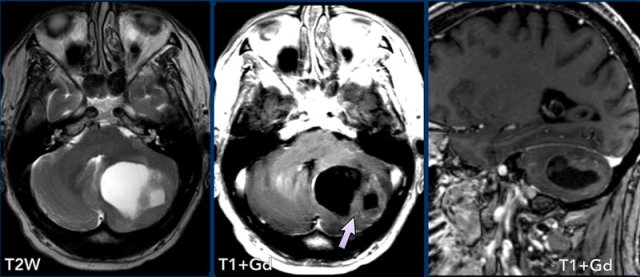

Here a more difficult case.

This is a patient, who presented with acute cerebellar

signs.

Images

On the T2W-image there is a hyperintense lesion, which shows rim enhancing after contrast

administration.

This is luxury perfusion in an enhancing subacute infarction.

Note also the older infarctions in the left cerebellar hemisphere.

When in doubt, follow-up imaging can help.